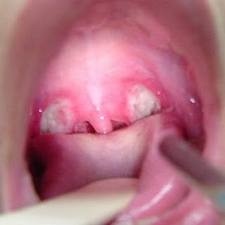

Amandel adalah dua kelenjar getah bening yang terletak di setiap sisi bagian belakang tenggorokan. Mereka berfungsi sebagai mekanisme pertahanan atau kekebalan tubuh. Amandel membantu mencegah tubuh dari berbagai infeksi. Ketika amandel terinfeksi. kondisi ini disebut tonsilitis.

Tonsilitis dapat terjadi pada semua usia dan paling umum terjadi pada infeksi masa kanak-kanak. Gejala tonsilitis termasuk sakit tenggorokan. amandel bengkak. dan demam.

• Amandel muncul dengan bengkak dan berwarana merah

• Amandel memiliki bintik-bintik putih atau kuning